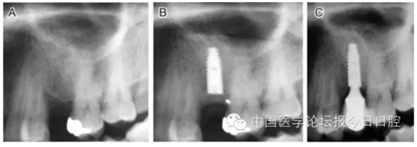

臨床上,可使用曲面體層放射線法及CT掃描方法對上額竇及可用骨量進(jìn)行評估。其中曲面體層放射線法可提供多數(shù)病例的硬腭致密影像,為治療計(jì)劃提供有價(jià)值的參考(圖1);而使用CT掃描可提供骨密度信息。如骨高度、密度、牙槽嵴的方向位置,皮質(zhì)骨和松質(zhì)骨的特點(diǎn),上頜竇黏膜厚度,病理狀態(tài)等。顯然,在上頜竇底提升術(shù)中,CT掃描影像的信息對于手術(shù)設(shè)計(jì)和減少治療風(fēng)險(xiǎn)非常重要。

圖1 采用曲面體層放射線法評估